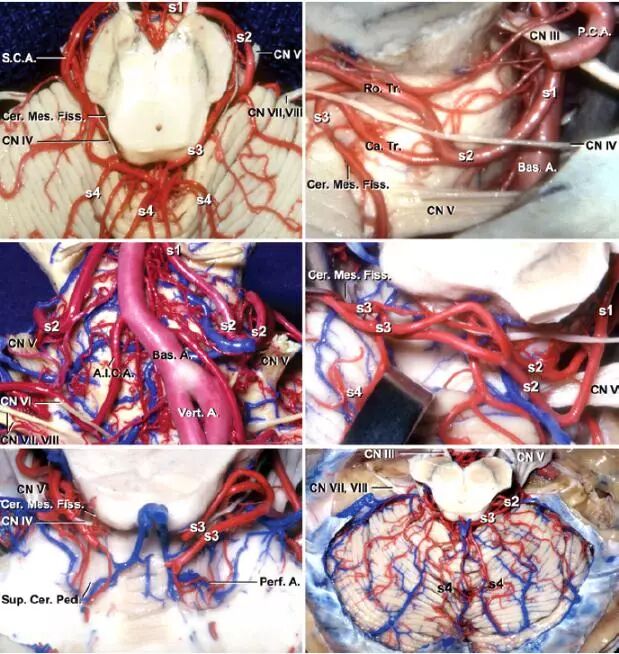

SCA包括四段:

1. 桥脑中脑前段(S1):在动眼神经下方从SCA起始处走行至脑干前外侧。

2. 桥脑中脑外侧段(S2):从脑干前外侧向尾侧走行至三叉神经根,进入小脑中脑裂。

3. 小脑中脑段(S3):在小脑中脑裂内伴行滑车神经,最终经发夹样弯曲到达天幕缘。

4. 皮质段(S4):从小脑中脑裂穿出,供应天幕面的小脑。

图1:图示SCA各段的解剖(AL Rhoton, Jr惠赠图片)。

注:S.C.A.:小脑上动脉。Cer.Mes.Fiss.:小脑中脑裂。CN Ⅳ:滑车神经。S4:小脑上动脉S4段。S1:小脑上动脉S1段。S3:小脑上动脉S3段。S2:小脑上动脉S2段。CN Ⅴ:三叉神经。CN Ⅶ,Ⅷ:面听神经。P.C.A.:大脑后动脉。CN Ⅲ:动眼神经。Bas.A.:基底动脉。Ro.Tr.:小脑上动脉头侧干。Ca.Tr.:小脑上动脉尾侧干。A.I.C.A.:小脑前下动脉。Vert.A.:椎动脉。Sup.Cer.Ped.:小脑上脚。Perf.A.:穿支动脉。